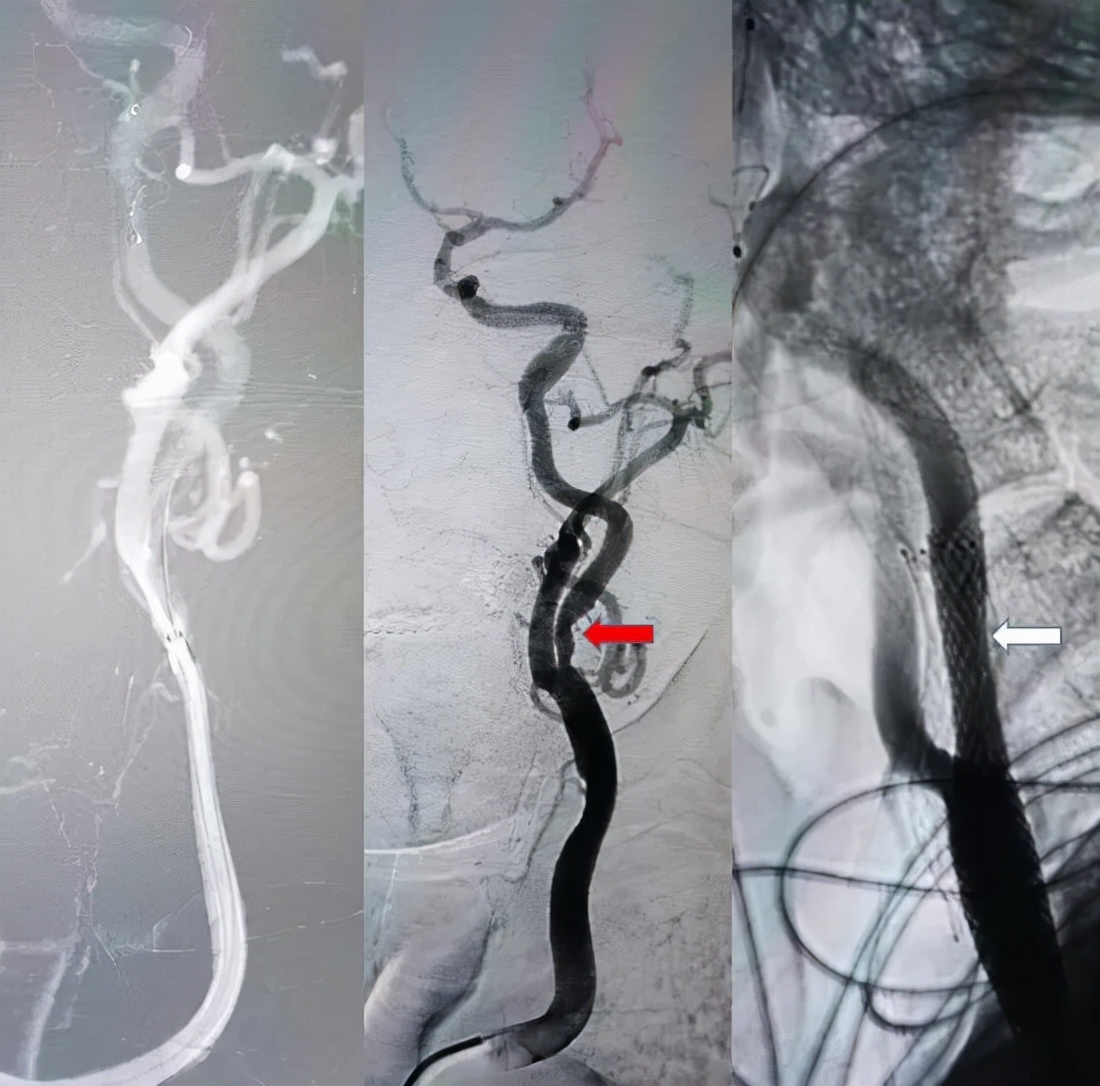

术中造影提示:左侧颈内动脉重度狭窄(红箭头);同期经桡动脉入路行左侧颈内动脉支架置入术,术后血管狭窄即刻解除(白箭头),手术过程非常顺利,术后患者在医护陪同下步行回病房。